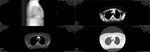

The culprit

This is the scan from mid October that identified my primary lung tumor. The smaller yellow spots you see around (excluding the mass in the middle) are metastasis that have spread to my bones.

The first scan

This is from the CT scan I got when I went to the ER for the second time for a persistent cough, chest pain, and difficulty breathing. A few hours after this imaging, they told me that they suspected it was cancer.